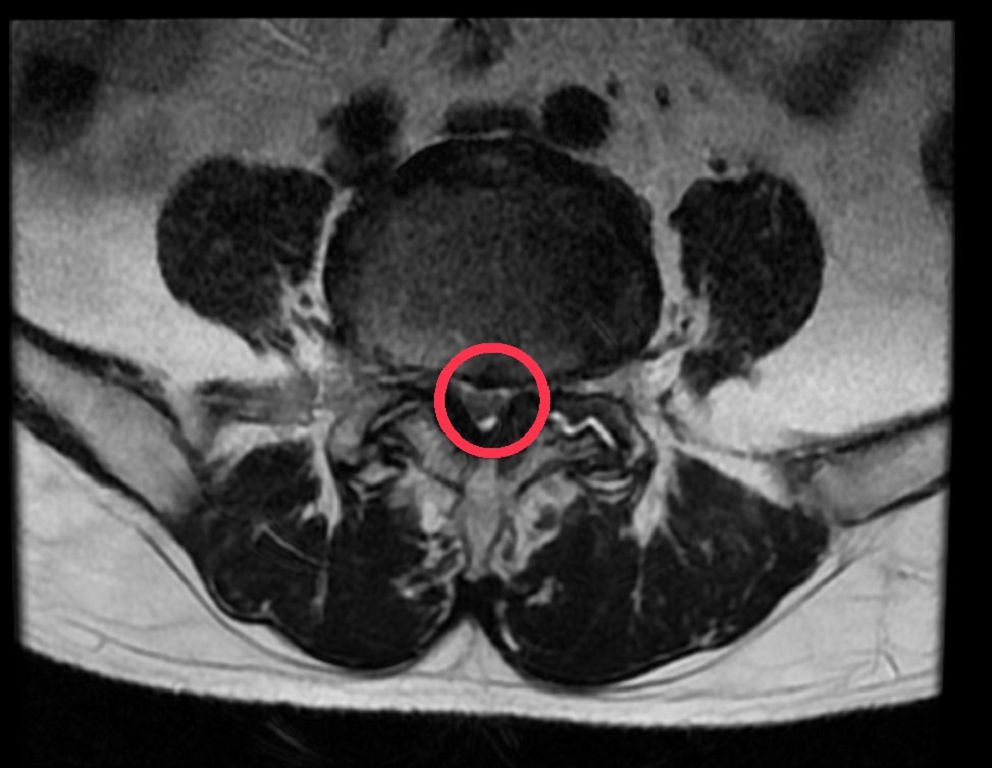

磁振造影顯示黃先生腰椎滑脫,神經受到壓迫。

洪祥益主任表示,經由腰椎X光及核磁共振造影檢查,發現黃先生第4、5節腰椎滑脫及嚴重壓迫神經,同時椎間盤突出,評估後建議以腰椎微創融合手術治療。微創融合手術可以保留肌肉,利用撐開器順著肌肉紋理建立手術路徑,減少組織破壞,不僅傷口小、術後疼痛感低,有助於加速恢復;傳統手術需將背部肌肉剝離,傷口較大、術後恢復較慢,且容易導致核心肌群肌肉萎縮纖維化、僵硬痠痛的後遺症。